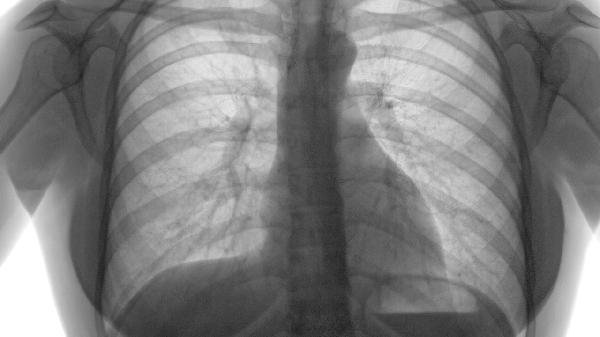

- 3 慢性阻塞性肺气肿该如何确诊